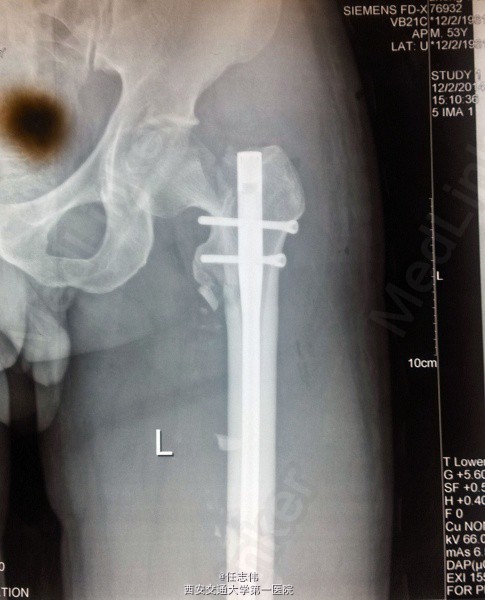

股骨干骨折术后发现股骨颈骨折,怎么处理?

53岁,男性,左股骨干骨折术后7月余 7月前因左股骨干骨折在当地医院行骨折复位髓内钉内固定术,术后复查片子是:股骨颈骨折。予以卧床制动观察

左股骨干骨折术后;左股骨颈骨折。

目前应该怎么处理? 再次手术?行髋关节置换?还是别的方法?